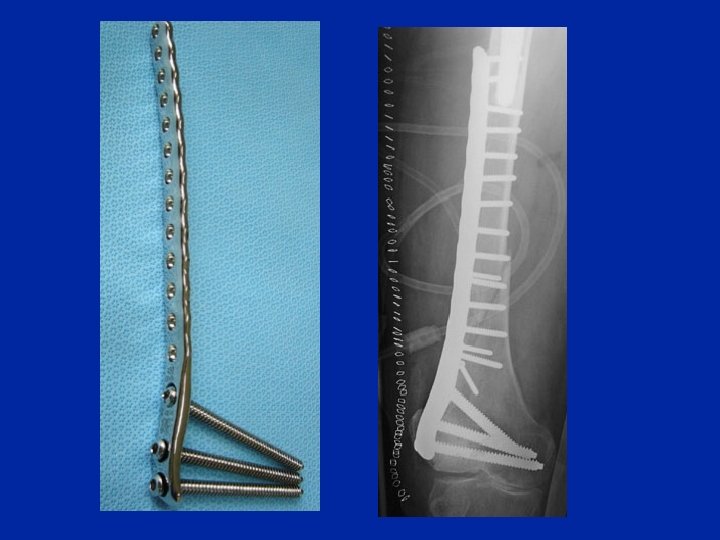

Fratture comminutive : ponteggio con placca

Placca

Placca da Chiron

Sistema di osteosintesi mediante placca applicata contro l’osso con una via di accesso piccola. Le viti sono posizionate mediante accessi cutanei guidati con un sistema esterno (Synthse)